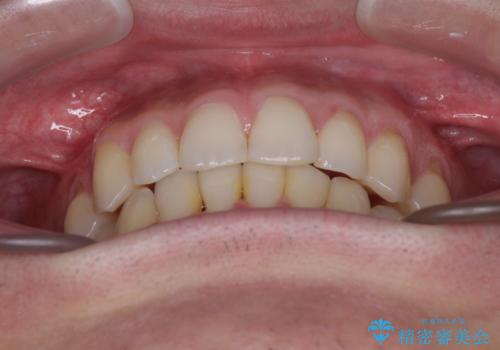

ディープバイトと叢生 インビザラインによる矯正治療

ディープバイトもデコボコも改善され、気になっていた銀歯もセラミックとなり、患者様には大変満足していただきました。

上顎奥歯の銀歯も気になっていたので、矯正治療の途中でセラミッククラウンへ変更し、その後歯列を仕上げていくこととしました。

上下ともに叢生が認められたため、親知らずすべてを抜歯し、歯列全体を後方へ移動させることで歯列を整えることとしました。